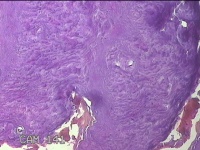

左腕掌侧结节

性别

男

年龄

57岁

临床诊断

皮下结节

一般病史

近3个月来,发现左腕掌侧一结节,无明显疼痛及不适。

标本名称

大体所见

灰白暗红色皮肤样结节1.5x0.8x0.3cm一个,表面糜烂,切面灰白暗红色,质软。

良性病变。